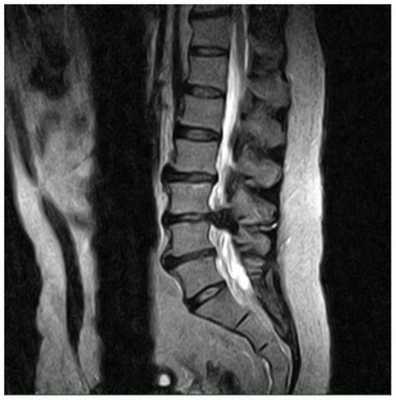

Межпозвонковая грыжа

Грыжа межпозвонкового диска возникает тогда, когда фиброзное кольцо прорывается и диск смещается в полость спинномозгового канала, сдавливая спинной мозг.

Своевременная диагностика грыж помогает избавить пациента от дискомфорта и боли. Проведение МРТ дает развернутую картину течения заболевания. На снимках можно увидеть локализацию грыжи, ее размер и степень пережатия спинного мозга, определить воспаление окружающих тканей.